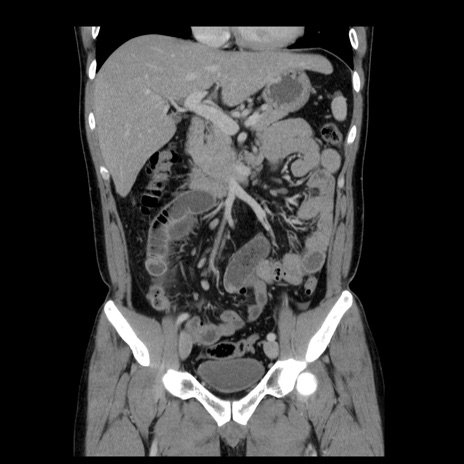

症例4(冠状断像)

【症例】30歳代男性

【主訴】腹痛、嘔吐

【現病歴】昨晩から突然の腹痛あり、その後嘔吐、軟便も出現。腹痛が改善しないため救急搬送となる。2日前にしめ鯖の食事歴あり。

【身体所見】意識清明、苦悶様、BP 135/90mmHg、BT 35.7℃、腹部:平坦、やや硬、心窩部〜臍部に自発痛、圧痛あり、筋性防御+、反跳痛-

【データ】WBC 8100、CRP 0.57